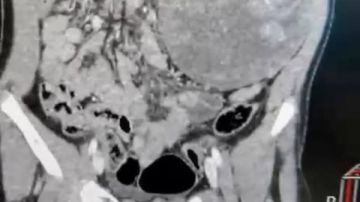

وبتدخل عاجل من الأطباء وبعد الفحوص والتحاليل تبين إصابة الطفلة بورم على الكلية وغدد متضخمة.

تدخل الفريق الطبي في جراحة عاجلة والمكون من جارحين متخصصين وجراحة عامة وتمكنوا من استئصال الكلية والغدد.

ومن التحاليل تبين أن الورم من نوع معين يصيب الأطفال وفي مرحلة متقدمة وبعد إستقرار حالة الطفلة تم تحويلها إلى المعهد القومي للأورام لاستكمال العلاج.